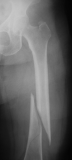

X-ray of right hip osteoporosis, age 54

Femur fracture

age 13